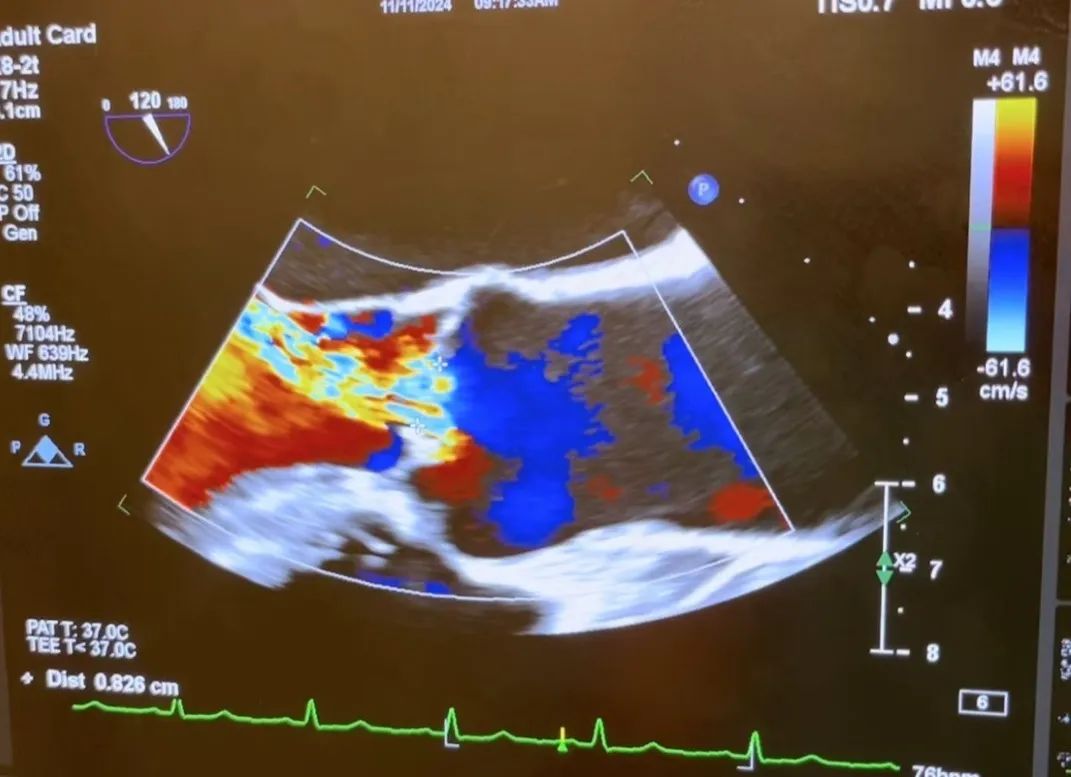

术前TEE评估显示重度主动脉瓣反流:

1.Vena Contracta Width=0.826cm

2.中心反流束宽度>65% LVOT

3.主动脉舒张期明显血流汇聚

4.左心室扩张

5.降主动脉显著的全舒张期血流逆转